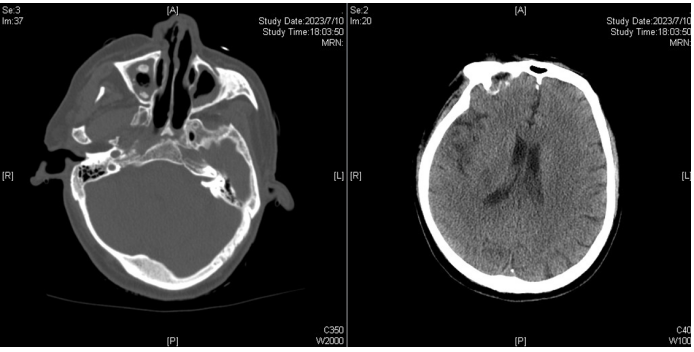

7月10日上午出现口齿不清,但对答切题,无肢体活动障碍等。下午出现嗜睡,左侧肢体活动度较右侧差;呼吸衰竭加重。完善头颅CT:脑实质未见异常密度,双侧上颌窦炎(图3),真菌感染可能。胸部CT:双肺感染较前加重,左上肺舌段、双下肺实变,双侧胸腔少量积液。

图片

图3  头颅CT